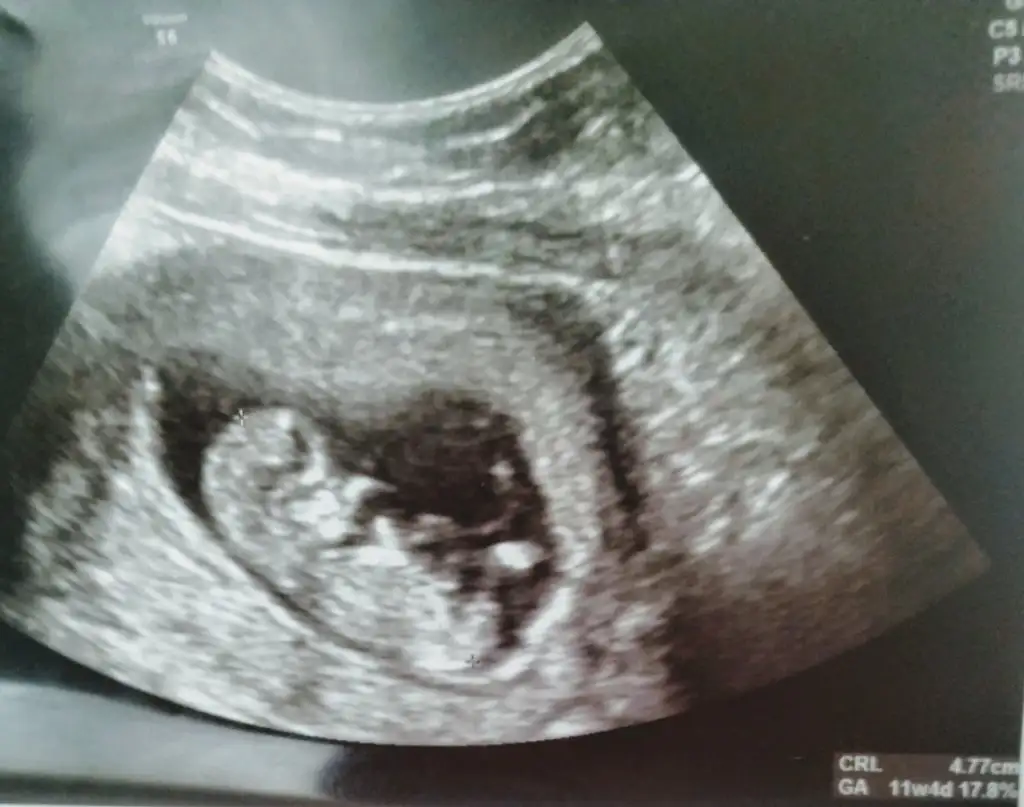

dr soylemeden siz gorun genital nub teorisi ( bebegin cinsiyeti)

Zaten12 haftalik. Ekledigim fotolar.

Tekrar baktım 12 haftalıga ne dik nede paralel pozisyon beni yanıtmıyorsa erkek gibi gibi diyorum😊 12 den buyuk usg sandım onun için 11 hafta istedim 3 bebek sanırım gönlünüzden geçen saglıkla nasip etsin rabbim gönlünüz ne diyor 😊